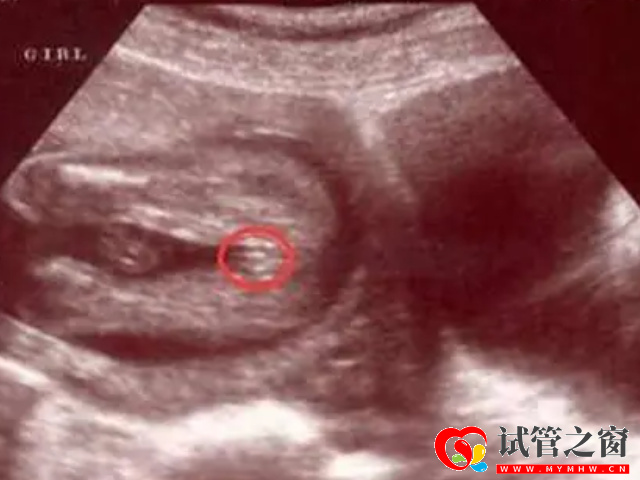

- 1. 可以看胎兒雙腿之間,如果說這個部位是有三條白線,而且呈小凹槽狀、圓圓的,大概率懷的是女孩,如果是凸出的東西,大概率是男孩;

四維彩超男女參照圖對比,一看有這個特征是男寶幾率最大

四維彩超看男孩女孩訣竅